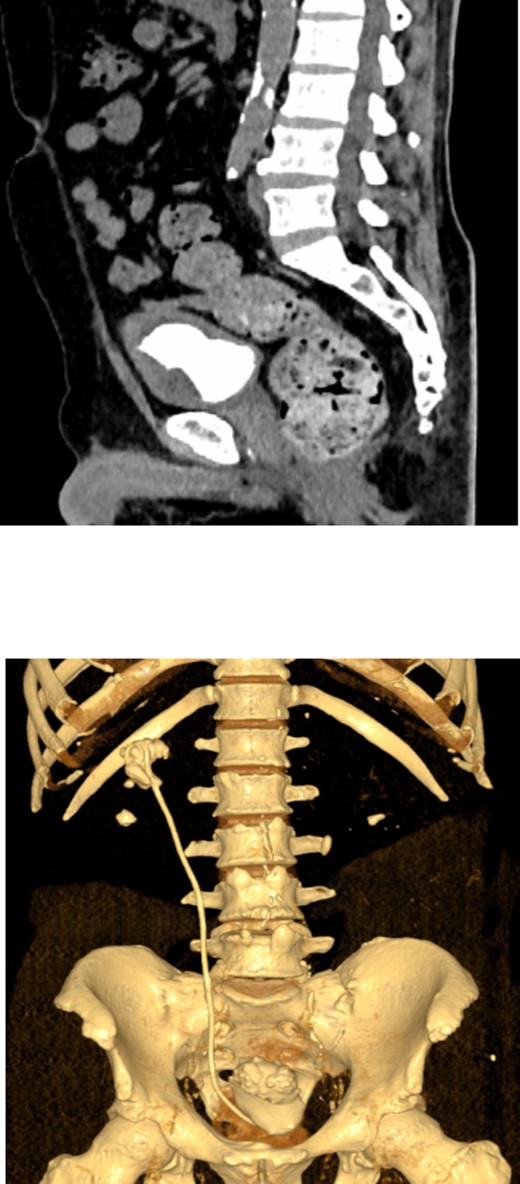

On physical examination, he had normal vital signs, no fever, and exhibited mild tenderness in the suprapubic area and right costovertebral angle. The results of the laboratory tests were normal, and the serum creatinine level was 0.8 mg/dl. Urine culture was negative for bacteria. Preoperative abdominal and pelvic ultrasound revealed two right renal stones, one measuring 4 cm in the upper pole and 2 cm in the lower pole with mild hydronephrosis, along with a large bladder stone measuring 6 cm, and a shadow of a double J stent. A computed tomography (CT) scan confirmed the presence of a 4 cm upper pole renal stone, a 1.8 cm lower pole renal stone, significant proximal pigtail calcification with mild hydronephrosis (Fig. 1A and B), and a 6 cm bladder stone deeply embedded in the distal pigtail (Fig. 2A and B). Additionally, small intrarenal stones were observed on the left side, along with a proximal ureteric stone measuring 8 mm by 9 mm with mild hydronephrosis.

Non-contrast CT scan showed intra-renal stone with significant proximal pigtail calcification and mild degree of hydronephrosis.